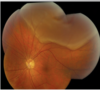

DESPRENDIMIENTO DE RETINA,CLÍNICA, CAUSA, DG Y TTO.

CLÍNICA:

FOTOPSIAS(PUNTOS BLANCOS)+ ENTOPSIAS(PUNTOS NEGROS)

DISMINUCIÓN DEL CAMPO VISUAL DE DOS FORMAS

- CAÍDA DE TELÓN (DESPRENDIMIENTO ES DE ARRIBA HACIA ABAJO)

- FORMACIÓN DE MURO( DE ABAJO HACIA ARRIBA)

DEFEECTO PUPILAR AFERENTE

CAUSAS RETINOPATÍAS + MIOPATIAS + TRAUAMA

DG: FONDO DE OJO

TTO: QUIRÚRGICO ( LA VITRECTOMIA.- CONSISTE EN SACAR EL HUMOR VÍTREO Y REEMPLAZARLO CON S. SALINA O CON GAS.

TROMVOSIS DE LA VENA CENTRAL DE LA RETINA, CLINCA, CAUSA DG Y TTO?

CLÍNICA:

AMAUROSIS SÚBITA+ PERIDIDA DE LA VISIÓN PARCIAL(VE COMO EN CUENTA DEDOS O SOMBRAS)

CAUSAS: RETINOPATÍA HIPERTENSIVA O TOMBOFILIA

DG: FONDO DE OJO

TTO: FOTOCOAGUALACION

DG:FONDO DE OJOS VEMOS = PALIDEZ + MÁCULA VISIBLE